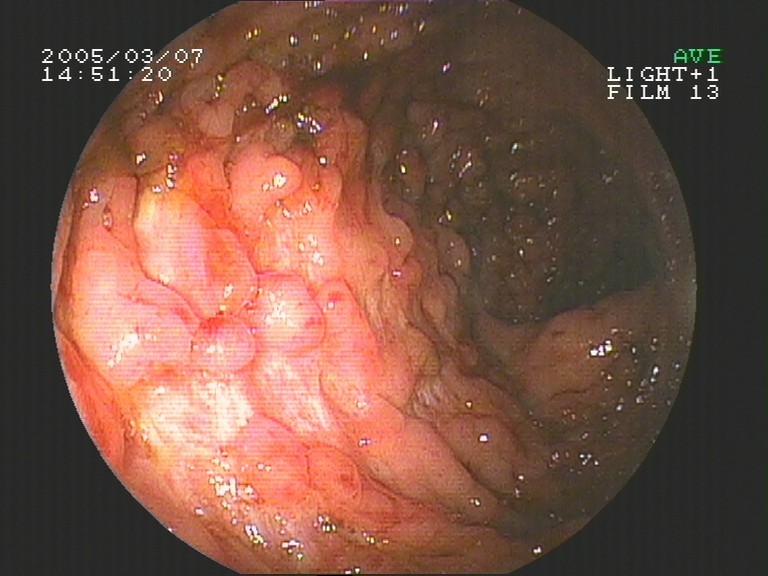

Coloskopie - Morbus Crohn